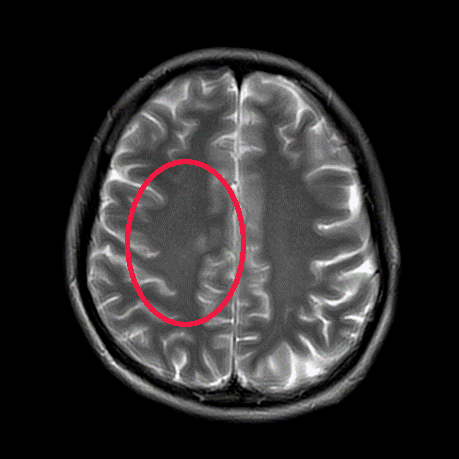

▲治疗前

▲治疗后1月

▲治疗后2年半

我们给这位年轻患者口服了靶向药

短短一个月

患者肺部和脑部肿瘤就出现明显退缩

随访至今

肺部、颅内、可见淋巴结、腹腔等

多处病灶完全缓解

患者日常生活无异于常人

我们对她能生存5年,甚至10年充满信心